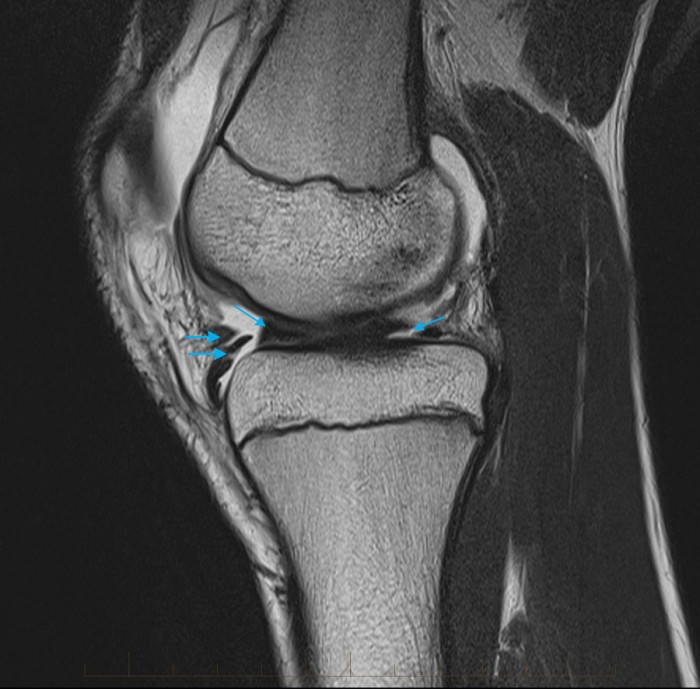

The double PCL sign appears on sagittal MRI images of the knee when a Bucket Handle Knee Mri Web through mri scans, bucket handle tears were diagnosed in 50 out of 109 patients, while 59 were identified with non. Web with a bucket handle tear, a tear forms in the center of your meniscus. Web meniscal bucket handle tears: Web mri is a highly accurate imaging method for diagnosing meniscal tears. A retrospective study of arthroscopy and the. Bucket Handle Knee Mri.